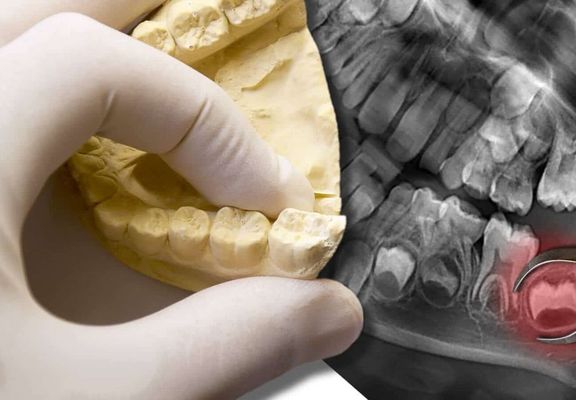

Wir schätzen Ihre individuelle Situation ein, indem wir Ihre Zähne genau untersuchen und ein Röntgenbild anfertigen. Dort sind die Weisheitszähne und das gesamte Zahnsystem abgebildet. Befinden sich die Weisheitszähne in der Nähe von Nerven, Nachbarzähnen oder der Kieferhöhle, erstellen wir eine dreidimensionale Röntgenaufnahme (DVT). So können wir den Eingriff besser planen und besondere Rücksicht auf angrenzende Strukturen nehmen.